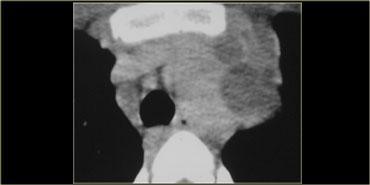

Hãy mô tả hình ảnh bên trái.

Sau đó tiếp tục.

Có một tổn thương dạng nang ở trung thất giữa.

Có mức dịch-dịch với hình ảnh sữa canxi (milk of calcium).

Nang đường ruột nguyên thủy đôi khi có thể chứa sữa canxi như trong ví dụ này về nang đôi thực quản.